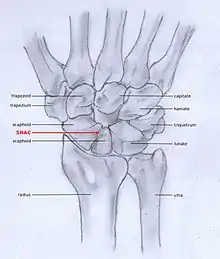

SNAC

Scaphoid non-union fractures changes scaphoid bone shape, which leads to abnormal joint kinematics. Due to lack of stability from the distorted scaphoid, a DISI can be developed.[3][6] Scaphoid Non-union Advanced collapse (SNAC) is the pattern of osteoarthritis that eventually develops by this process.

SLAC and SNAC are two patterns of wrist osteoarthritis, following predictable patterns depending on the type of underlying injury. SLAC is caused by scapholunate ligament rupture, and SNAC is caused by a scaphoid fracture which does not heal and because of that will develop in a non-union fracture. SLAC is more common than SNAC; 55% of the patients with wrist osteoarthritis has a SLAC wrist.[4]